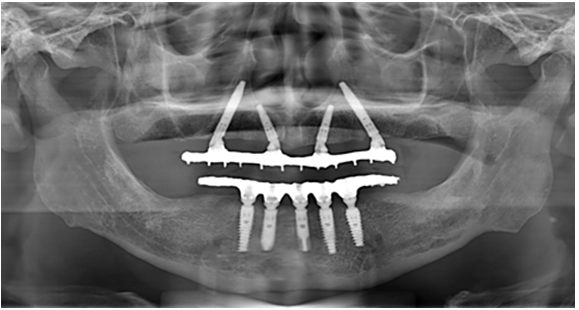

Clinically, the patient presented aesthetic and functional impairment and excessive exposure of the gingival tissue. The patient wore a removable partial denture that presented a mismatch, and only teeth #11, #12, #13, #14, #15 and #21 were present, with grade III mobility. The lower arch presented a fixed full arch hybrid prosthesis previously placed (Figure 1).

Radiographically, the patient had a partially edentulous upper arch, generalized bone loss, low quality bone (type III) and pneumatization of the right maxillary sinus (Figure 2.A).

After anesthesia of the upper jaw, an incision was performed in the bone crest followed by a buccal and palatal detachment of a flap from the right molar to the left molar. Horizontal osteotomy was performed to avoid esthetics and functional problems. The implant sites preparation was carried out according to the manufacturer's instructions. Perforations were initiated by the initial drill, followed by the drills 2.0mm, 3.5mm, 2.8/3.5mm and 3.75mm, with undersized site preparation technique. Two 3.75 x 20mm GM Helix Long Neoporos implants (Neodent, Curitiba, Brazil) were placed in the regions of teeth #15 (Figure 3.A) and #25 and two 3.75 x 13mm GM Helix Acqua implants (Neodent) in the regions of teeth #12 and #22. The four implants were placed 2mm subcrestally and anchored apically in the region of the paranasal bone with an insertion torque of 60 N.cm.

Due to the high initial implant stability obtained, it was possible to apply the immediate loading technique. Two GM Mini Conical Abutments of 30 degrees with 2.5mm transmucosal height (Neodent) were used on the implants of sites #15 and #25 and two GM Mini Conical Abutment of 17 degrees with 2.5mm transmucosal height (Neodent) were used in implants of sites #12 and #22 (Figure 3.B). The upper arch was sutured with 5.0 resorbable suture thread. Then, four open-tray impression copings were placed on the abutments and joined to the multifunctional guide in occlusion with the lower arch using Pattern acrylic resin (GC America Inc, Alsip, USA). The impression was performed with condensation silicone Speedex (Coltene, Altstätten, Switzerland) and sent to the prosthesis laboratory.

Forty-eight hours thereafter, the teeth were tried in, fixed with wax to the metal bar and on the third day the final prosthesis was inserted, according to the passive fit technique. Occlusal adjustments were performed, relieving excessive contact in excursive movements during the osseointegration period, but keeping the prosthesis in occlusion (Figure 4.A, Figure 4.B and Figure 5).

The patient returned with 14 days post-surgery to remove the suture and assess the clinical and radiographic condition of the rehabilitation. After 30 days and 6 months, success of implants and rehabilitation, favorable remodeling of the peri-implant tissues and satisfactory aesthetic and functional conditions were observed (Figure 6 and Figure 7).